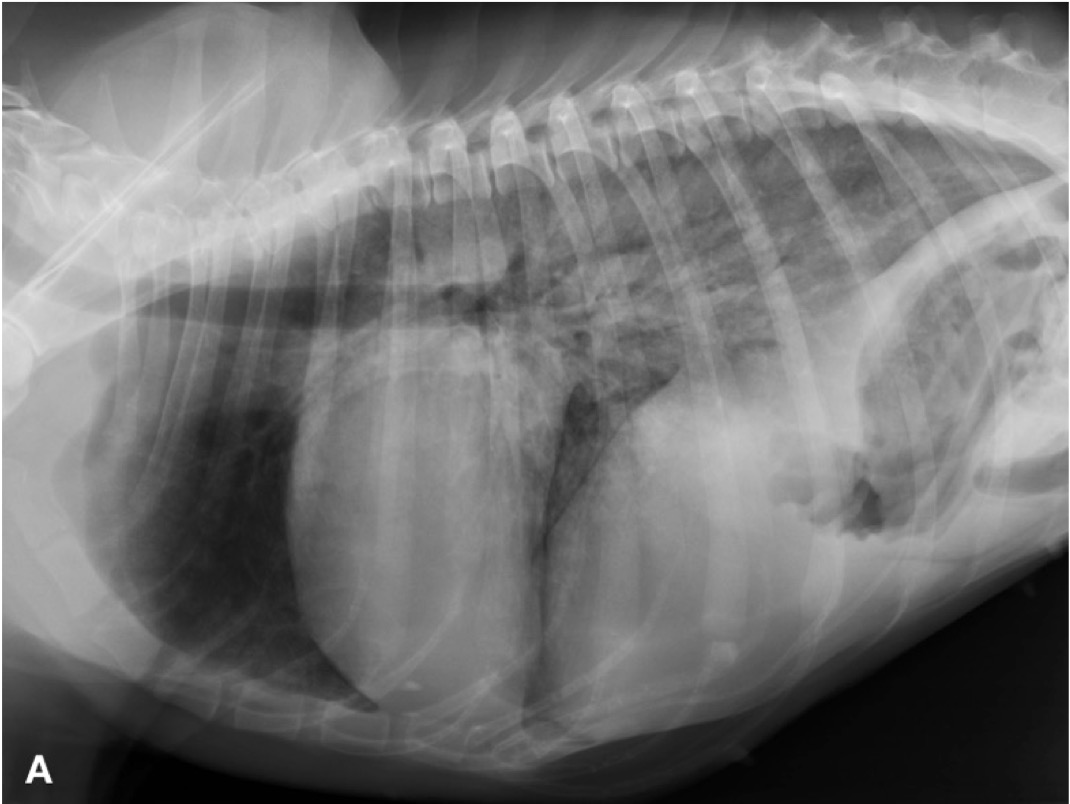

L’esame radiografico di norma si può eseguire senza sedazione; si può eventualmente eseguire una breve anestesia gassosa con induzione diretta. Viste le dimensioni della cavia, conviene eseguire di routine le proiezioni laterale e ventrodorsale di tutto il corpo, a meno che l’animale non sia gravemente debilitato e manovre stressanti poss...